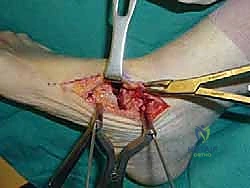

1. الشقوق الجراحية (Incision & Approach)

يتم إجراء شقين جراحيين للوصول إلى المفاصل الثلاثة:

* شق خارجي (Lateral Incision): للوصول إلى المفصل تحت الكاحل والمفصل العقبي المكعبي.

* شق داخلي (Medial Incision): للوصول إلى المفصل الكاحلي الزورقي.

يحرص الدكتور هطيف على حماية الأعصاب والأوعية الدموية الحساسة المحيطة بالمنطقة.

3. تصحيح التشوه (Deformity Correction)

بمجرد تحرير المفاصل، يقوم الدكتور هطيف بإعادة ترتيب العظام يدوياً لإصلاح التشوه. إذا كانت القدم مسطحة، يتم رفع القوس. وإذا كانت مقوسة للداخل، يتم تعديلها لتصبح مستقيمة. الهدف هو الحصول على قدم مستوية تماماً (Plantigrade Foot) توزع وزن الجسم بالتساوي.

4. الترقيع العظمي (Bone Grafting - إن لزم الأمر)

في بعض الحالات التي يوجد فيها فجوات عظمية أو قصر في العظام، يتم استخدام طعوم عظمية (تؤخذ غالباً من عظم الحوض للمريض أو من بنك العظام) لملء الفراغات وتحفيز التئام العظام (Osteogenesis).